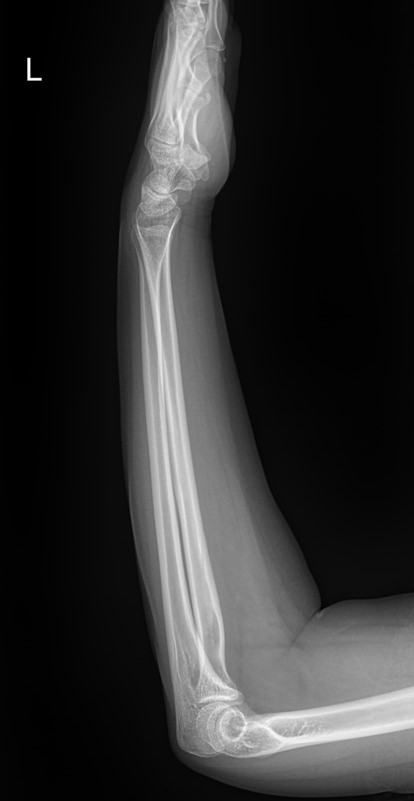

В предплечье входят 2 кости ― лучевая и локтевая. Вместе они соединяют кисть с плечом и обеспечивают движение и повороты руки. Переломы костей происходят в наиболее тонких местах ― ближе к суставам. Реже встречаются костные и мышечные патологии и онкология.

Обследование поврежденного или пораженного предплечья начинают с рентгенографии. Современное оборудование несет минимальное количество обучения и позволяет делать несколько снимков подряд, например, для контроля хирургического лечения. В снимок кроме собственно локтевой и лучевой кости попадают оба смежных сустава ― локтевой и лучезапястный. Также видны и мягкие ткани.

Что покажет рентген предплечья

• Костно-травматические изменения лучевой и локтевой костей;

• Патологические изменения в костной ткани;

• Состояние мягких тканей;

• Состояние прилежащих суставов, их заболевания и травмы;

• Новообразования и метастазы данной области.